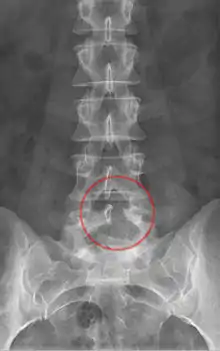

- يجرى قطع الصفيحة الفقرية القطنية على الفقرات القطنية، أي الفقرات الأقرب إلى العجز.

أثناء قطع الصفيحة الفقرية، يستلقي الفرد على بطنه ويوجه ظهره نحو الطبيب. يجرى شق أولي أسفل منتصف الظهر للكشف عن الفقرات التي سوف يُطبق قطع الصفيحة الفقرية عليها. في هذا الإجراء، يبقى الناتئ الشوكي وأربطة العمود الفقري سليمة، ولكن يجب فصل العضلات المجاورة للعمود الفقري والمعروفة باسم العضلات المحيطة بالنخاع (على سبيل المثال: العضلة الناصبة الشوكية) عن الناتئ الشوكي والقوس الفقري. في عملية القطع أحادية الجانب، تُفصل هذه العضلات فقط على الجانب الذي يُطبق فيه الإجراء. في عمليات قطع الصفيحة الفقرية ثنائية الجانب، تزال هذه العضلات على جانبي الفقرات. تُزال الأربطة التي تصل الصفائح الفقرية للفقرتين العلوية والسفلية، والتي تُعرف باسم الرباط الأصفر، في أغلب الأحيان أو يُعاد تشكيلها في هذا الإجراء للتكيف مع الكمية الصغيرة المستأصلة من العظام. باستخدام مجهر أو منظار داخلي لتأمين الرؤية خلال الإجراء، يستخدم مثقاب جراحي صغير لإزالة جزء من العظم من صفيحة واحدة أو الصفيحتين من الفقرات. يمكن إجراء قطع الصفيحة الفقرية على فقرات متعددة ضمن العملية الجراحة نفسها؛ تُعرف هذه العملية بقطع الصفيحة الفقرية متعدد المستويات.

يتواجد نوع من قطع الصفيحة الفقرية مختلف قليلًا ولكن شائع الاستخدام وهو قطع الصفيحة الفقرية أحادي الجانب لتخفيف الضغط الثنائي عن النخاع الشوكي. يستخدم هذا الإجراء طفيف التدخل أغلب الأحيان لعلاج المرضى الذين يعانون من الانضغاط الشديد واجب العلاج في العمود الفقري. يحافظ هذا الإجراء على سلامة الأربطة الشوكية لكن يجب فصل العضلات المحيطة بالنخاع. يجرى قطع الصفيحة الفقرية أحادي الجانب على صفيحة واحدة من الفقرة. يؤمن استئصال العظم من صفيحة واحدة مدخلًا إلى القناة الشوكية. يستخدم مجهر أو منظار داخلي لتأمين الرؤية خلال الإجراء، تدخل الأدوات الجراحية من خلال هذه الفتحة في القناة الشوكية. تُحرك الأدوات الجراحية بعد ذلك أسفل الناتئ الشوكي وعبر القناة الشوكية للوصول إلى الصفيحة المقابلة على الجانب الآخر من الفقرة لقطع الصفيحة الفقرية الثانية. يكون الشق الجراحي اللازم لهذا الإجراء أصغر، إذ يحتاج الأطباء إلى الوصول إلى صفيحة واحدة فقط لإجراء قطع الصفيحة ثنائي الجانب، أي إزالة العظم من الصفيحتين ضمن فقرة واحدة. طُورت عملية قطع الصفيحة الفقرية أحادي الجانب لتخفيف الضغط الثنائي عن النخاع الشوكي منذ ما يقارب 20 عامًا، وهو علاج جراحي ناجح شائع لتضيق العمود الفقري القطني.[4]